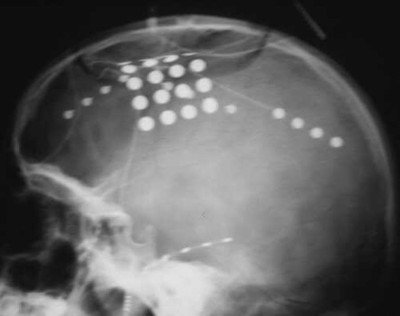

Cirugía contra la epilepsia

Envíado por Dr. Mauricio Ernesto Palacios Marchesini